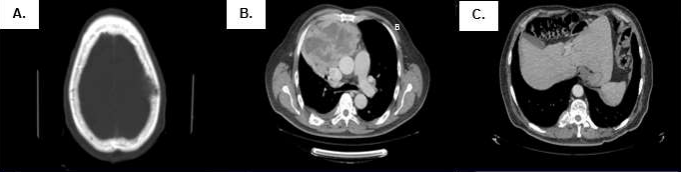

Male patient, 58 years old, native and from Cerro de Pasco. He had oncological family history of mother who died of tonsil cancer. He refers a time of illness of 11 years with a diagnosis of pulmonary cyst, of approximately 50 mm and, with surgical possibility; however, the patient refused surgery and only continued in controls. Such lesion was growing over the years, causing mild chest pain and, in recent months, mild dyspnea and weight loss, so he was referred in April 2016 to the Medical Oncology Service, bringing imaging tests that evidenced a mediastinal widening and a mediastinal mass (Figure 1A y 1B).

Figure 1: (A) PA chest X-ray (04/24/16) with widening of the mediastinum ocuppied by a radiopaque image. (B) Thorax tomographic scan (04/25/16) with mass-like imaging dependent on the mediastinum, no evidence of adequate cleveage plane.